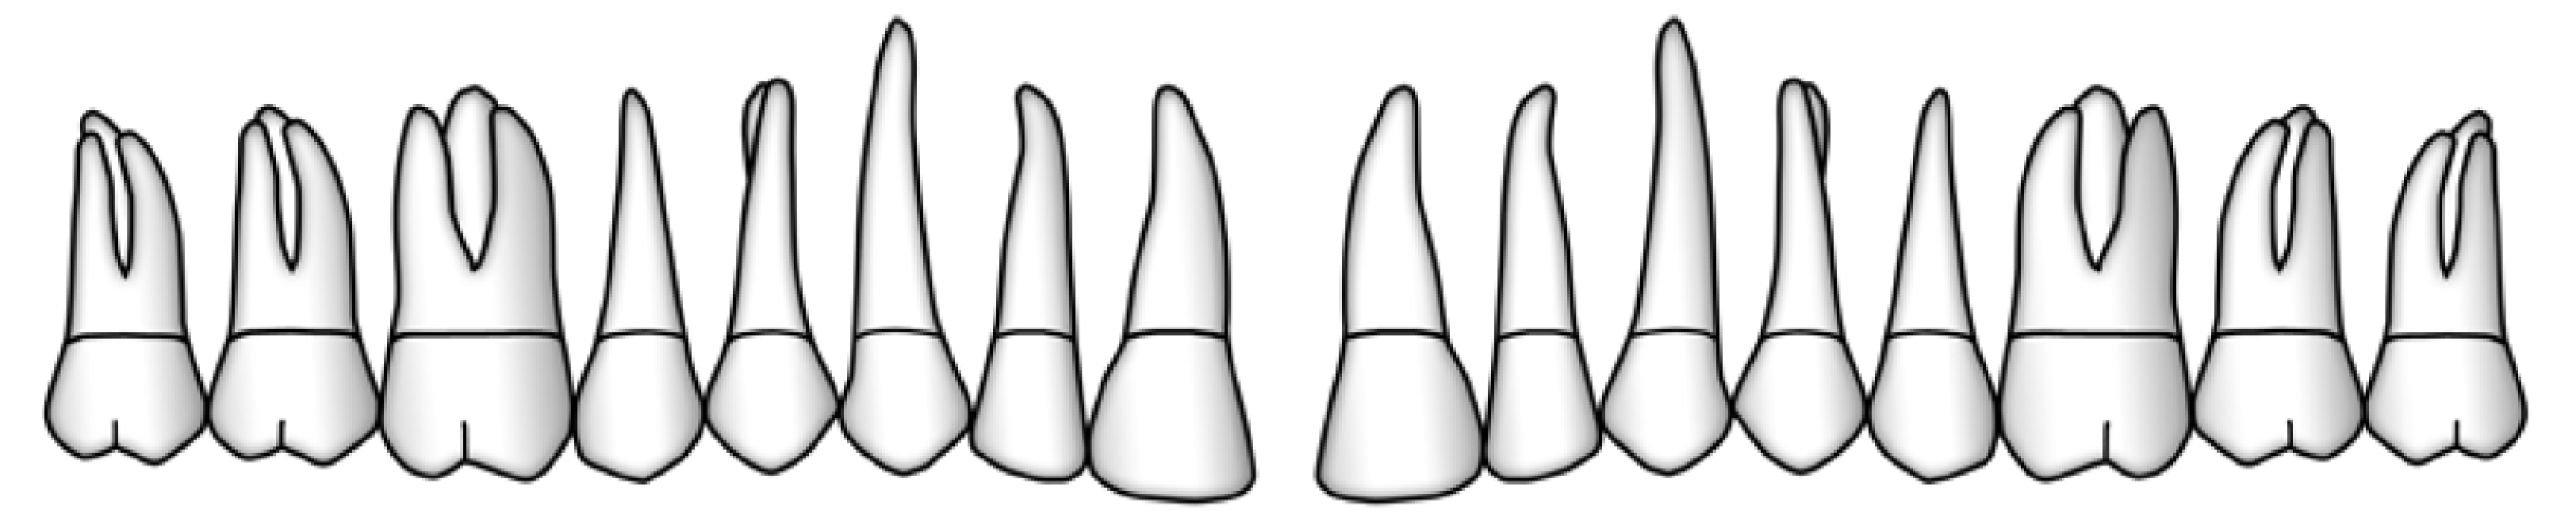

Sechs Messstellen pro Zahn oder Implantat

Entscheidend für die Aufzeichnung sämtlicher parodontalen oder periimplantären Messungen ist die Wahl der richtigen sechs Stellen um den Zahn oder um das Implantat. Hierfür wird der Zahn oder das Implantat von okklusal betrachtet in seinem Umfang in 6 Abschnitte eingeteilt. Für jeden dieser Abschnitte wird die Stelle mit dem höchsten Sondierungswert ermittelt und ausgemessen.